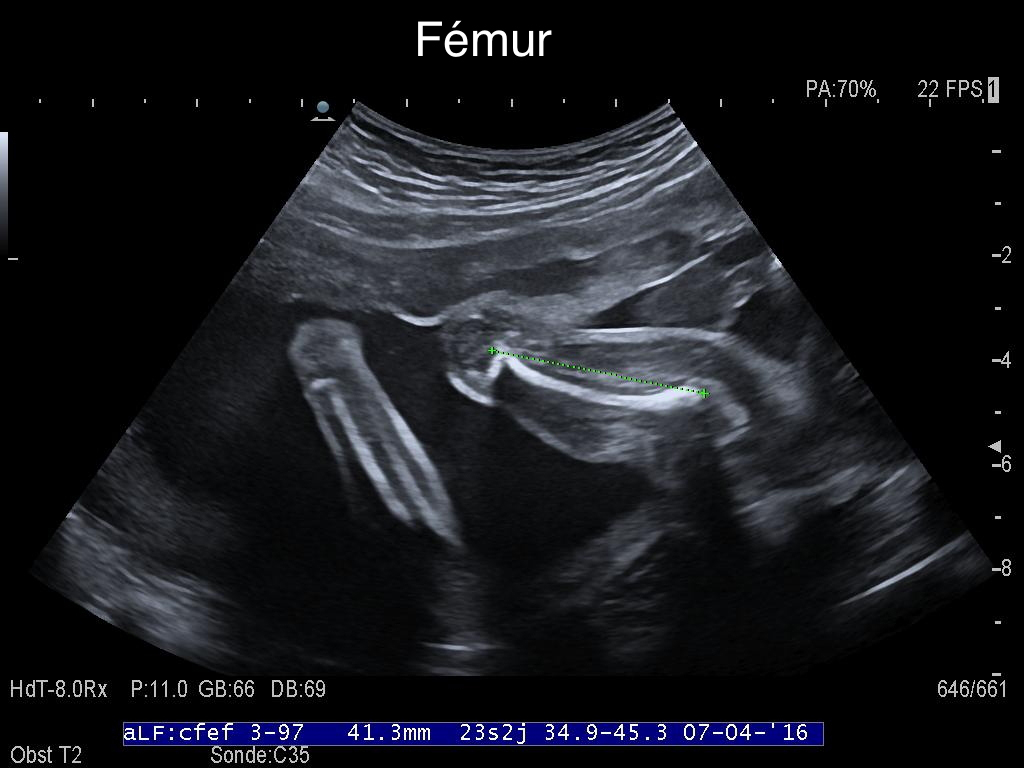

-de vérifier le bon développement et la bonne croissance de votre fœtus. Pour cela des mesures de plusieurs structures (de façon systématique : diamètre et périmètre crânien, périmètre abdominal et longueur du fémur) sont effectuées. Ces mesures seront reportées sur des courbes, ce qui permettra d’apprécier la croissance de votre fœtus. Dans certaines circonstances (petit fœtus, antécédents personnels ou familiaux…) des mesures complémentaires peuvent être réalisées ;